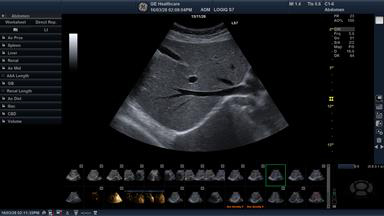

LOGIQ S7 with XDclearによる診断画像

昨年10月に発売を開始した「LOGIQ S8 with XDclear」に搭載されている日野本社開発の高感度プローブ「XDclearプローブ」は,CTやMRIと比べ視野深度が限られるという超音波検査の課題を克服し,体の浅部から深部にいたるまでの画質向上を実現した。今回発売する「LOGIQ S7 with XDclear」にも同プローブを搭載し,さらに,23インチの大型ワイドモニターの採用により,横から見る際の画像認識も 容易になり,超音波診断にかかわる医師・技師の負担軽減が期待される。加えて,モバイルバッテリーの内蔵により電源をつながず院内のどこにでも持ち運び検査ができる「オフラインスキャン」も実現した。従来2~3分はかかっていた立ち上げ時間をなくすことで,ケアサイクルの向上にも役立つと注目されている。

同社では,GEヘルスケアの中核開発・製造拠点として,これまで30年以上にわたり世界の医療現場に日本発の先進プローブを届けてきた開発・製造チームの密な連携のもと,プローブの素材を見直し,従来のセラミックに替えて,電気信号と音の変換効率に優れたシングルクリスタル(高密度単結晶)を採用し,これまで使用されていなかった音響エネルギーを有効活用するアコースティックアンプリファイヤー技術,ならびにレンズ表面での温度上昇を抑えてプローブが最大限の性能を発揮できるようにするクールスタック技術を搭載することで,この課題を克服。画質と診断深度の両立を可能にするXDclearプローブの開発で,皮膚に近い表在部から体内深部まで広範囲にわたる画質向上を実現した。